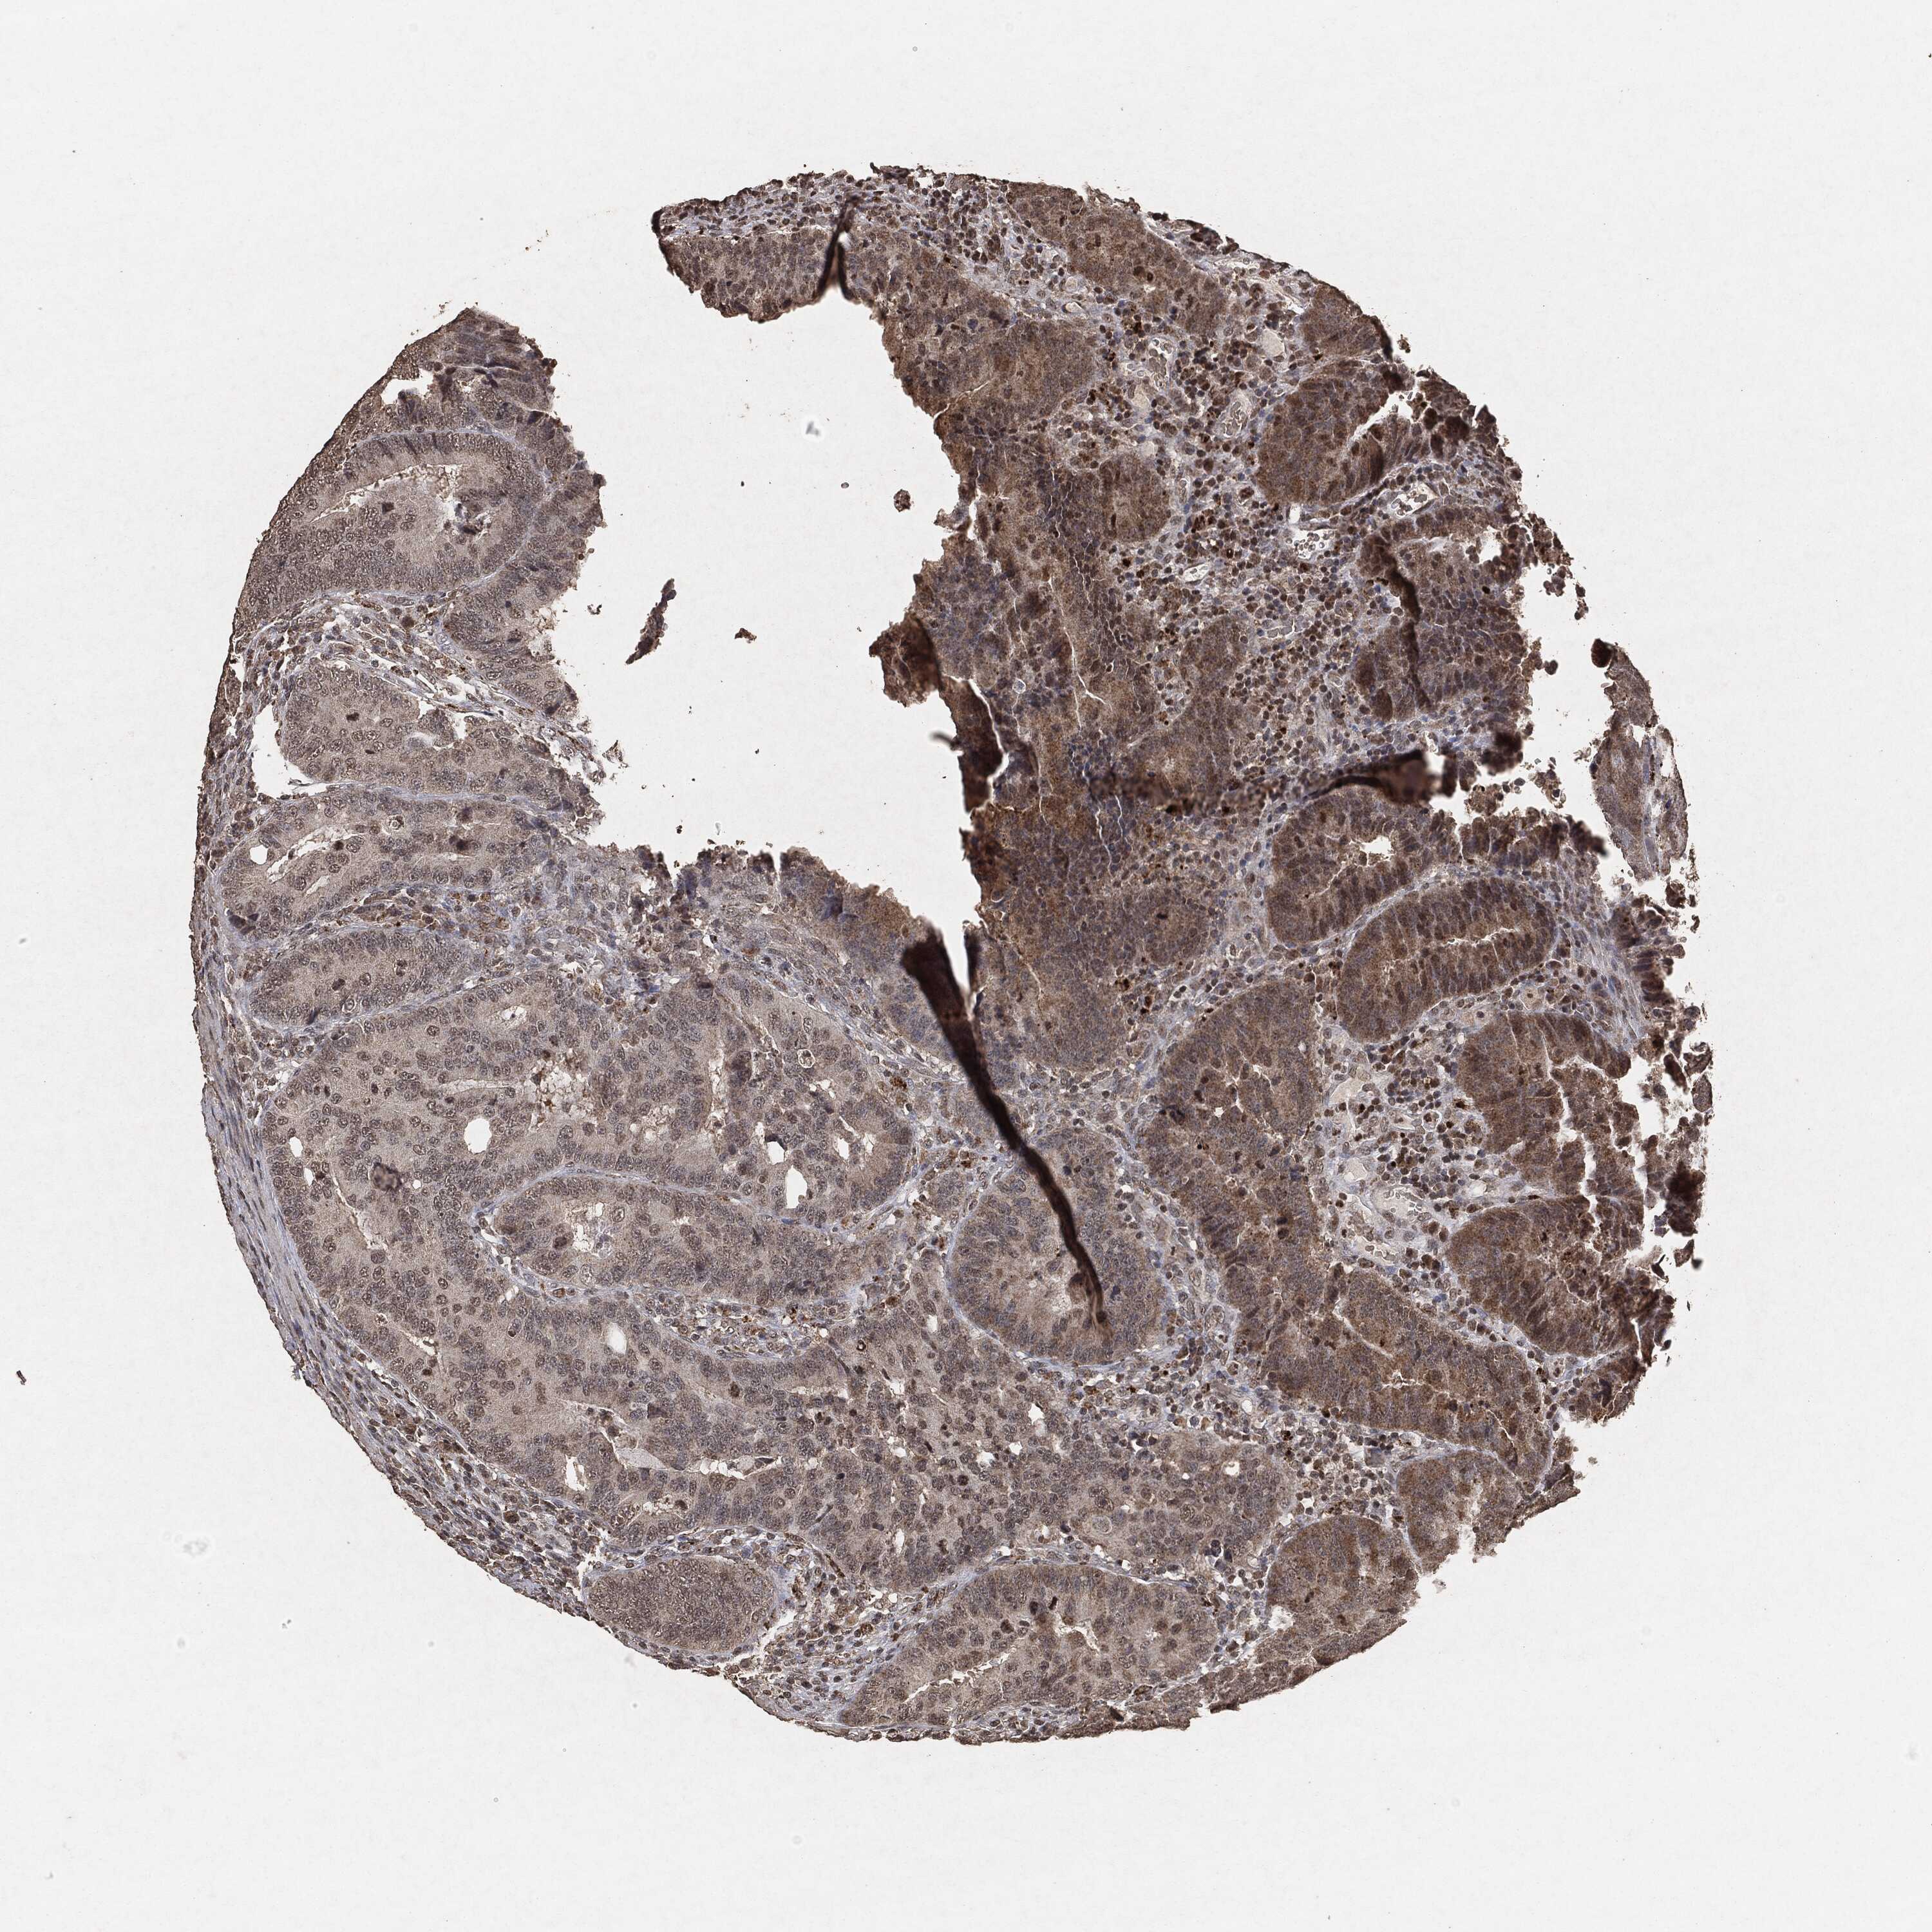

CANCER COLORECTAL CANCER Show tissue menu

Colorectal cancer

Human cancer

Colon adenocarcinoma